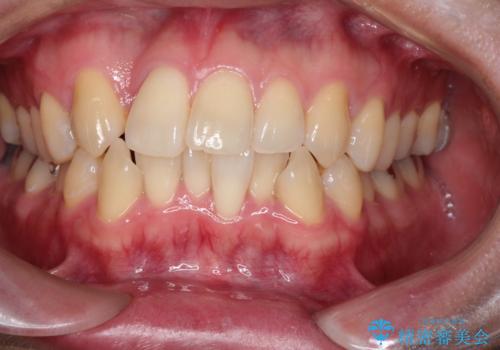

- 「歯のデコボコと前歯が引っ込んでいるのを治したい」を主訴に来院された患者様です。

デコボコの量が多かったため上下左右4を抜歯してワイヤー矯正で治療を行いました。

正面から見たときに右上2が全く見えないくらい、右上2が後ろに引っ込んでいる状態でしたが綺麗に並べる事が出来ました。